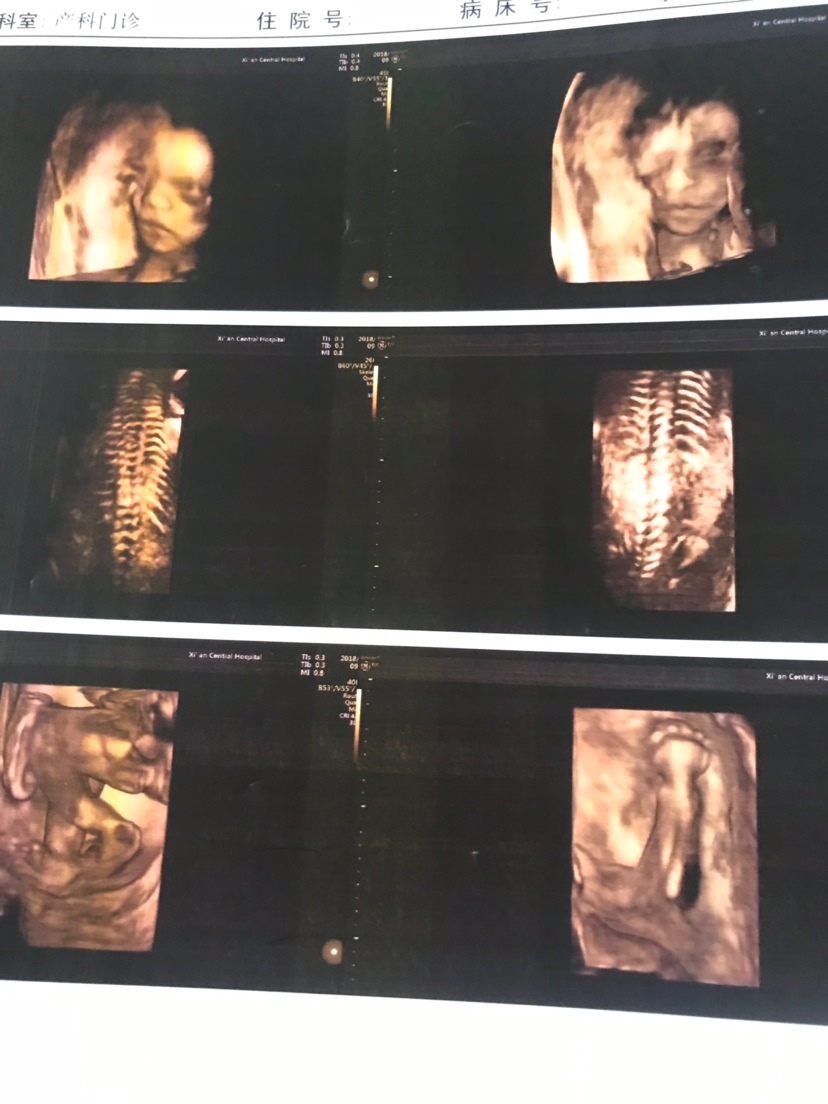

孕17周+5天